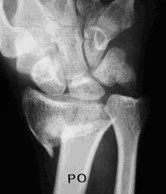

Arthritis Wrist and Forearm Childrens Wrist Fractures Colles Fractures Colles Surgery Chronic Forearm Compartment Syndrome De Quervains Syndrome Kienbocks Disease Scaphoid Fractures Scpholunate Ligament Tears TFC Tears Wrist Arthritis - Salvage Procedures Wrist Arthroscopy Wrist Exercises Wrist Xrays - Radiographers